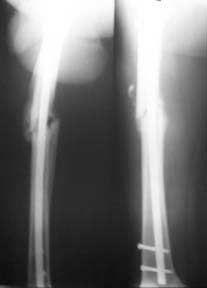

Here are the post op pictures.

To recap: Middle aged male patient on whom a heavy log fell and sustained injury. Had pelvic ring disruption with fracture femur. Ext fix of pelvis and interlocking nailing of femur done. Developed compartment syndrome thigh and had fasciotomy. Went on to rhabdomyolysis and ARDS. Managed with ventillation and alkalinising. Fasciotomy wound later skin grafted.

Now what I have not told so far: At about three weeks after the injury when patient had recovered from the problems described above developed acalculous cholecystitis. As he was being prepared for surgery he suddenely collapsed and went into shock. Required resuscitation and inotropic support. After vital signs were stable he was taken up for laparoscopic cholecystectomy. On introducing the scope it was found that there was a gangrenous gall bladder with lots of inflammation all around. It was converted to an open cholecystectomy. Ventillated post op. Patient's ext fix on pelvis was removed after six weeks and ambulated with walker. Had developed a deep sacral pressure sore. Discharged with home care of pressure sore and ambulation with support. Now at about three weeks the femur is uniting, pelvis stable and the pressure sore healing. Patient changed to axillary crutches from walker.